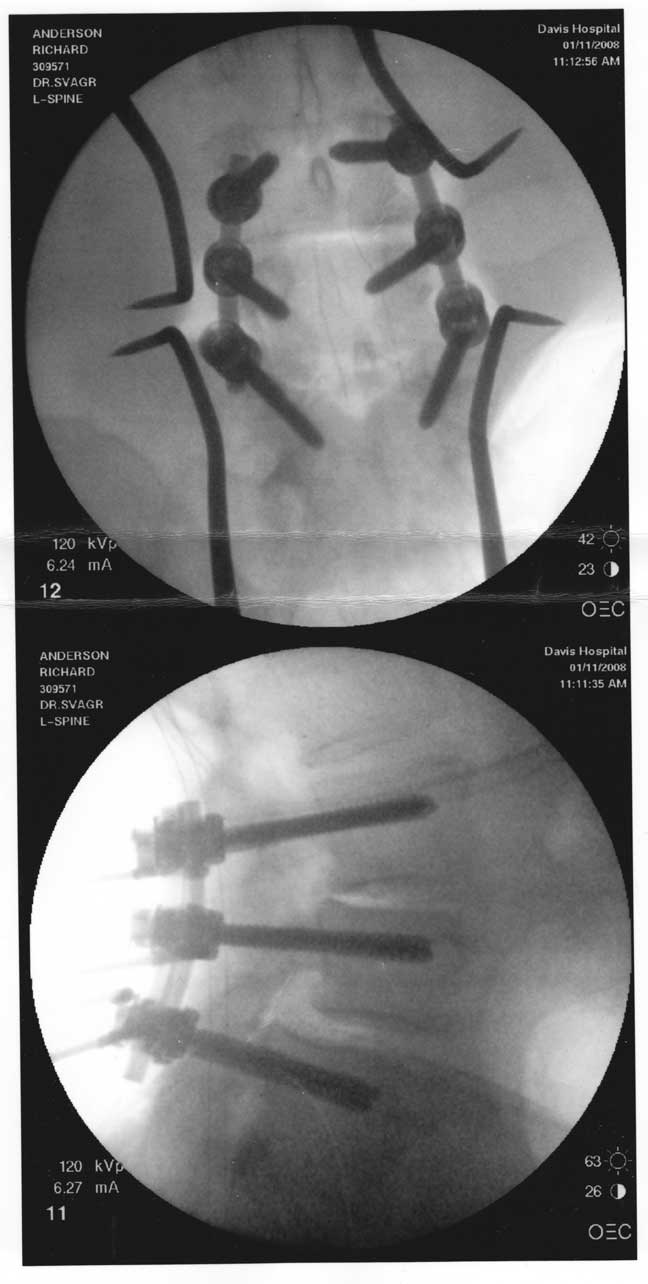

![]() Fusion hardware, installed January, 2008 |

When the pain subsided, I made my way to the Kaiser-Permanente group medical practitioners we infrequented as a benefit of Pappy’s employment at Valley College. They took x-rays and delivered what has turned out, apparently, to be an accurate diagnosis: degenerative lumbar spondylolysis, apparently hereditary (or at least not resulting from any known injury or malformation). In English, my otherwise well-behaved vertebrae tend to flake off little sharp bits which migrate to the base of my spine, where they work mischief upon the nerves that control my legs. “Have a nice life,” said the Kaiser minions: there’s really nothing we can do.” |